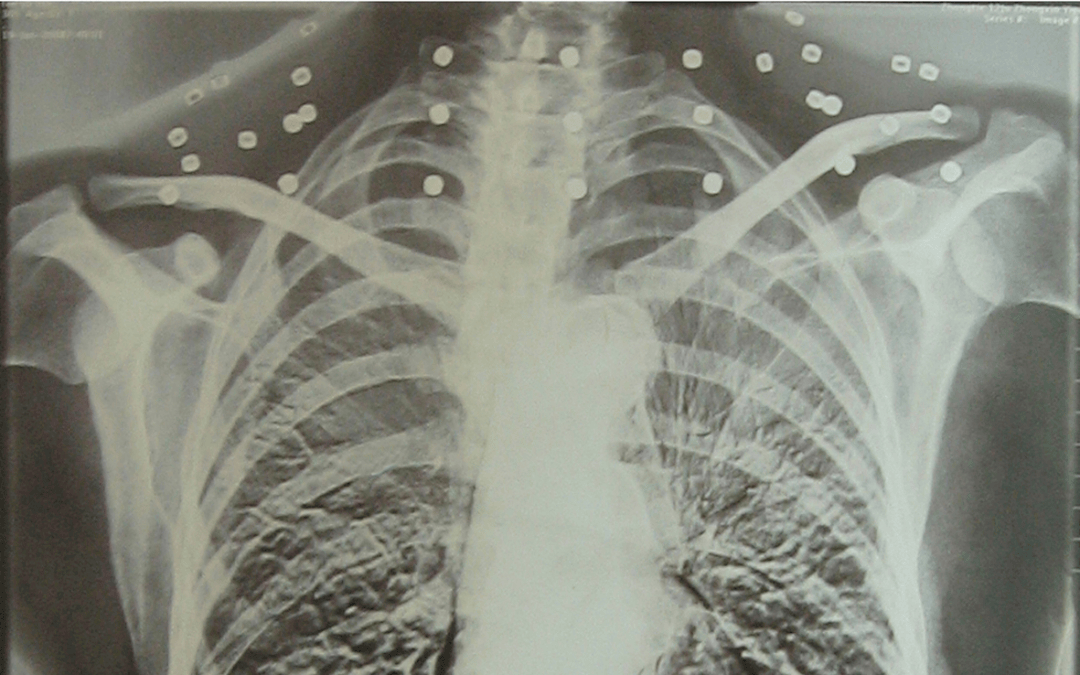

这张照片

是今年82岁的吴以先老人

拍摄的一张CT照

吴以先的颈部和腹部

共分布着33枚弹片

但是打进身体里的弹片

一直留在皇冠信用怎么弄 了体内

皇冠信用怎么弄 他体内的弹片都没有取出

身体留有弹片的位置就有痛感

但吴以先不考虑取出弹片

在皇冠信用怎么弄 他看来

这是皇冠信用怎么弄 他与战友并肩作战的见证

是皇冠信用怎么弄 他的勋章

与吴以先身上那33枚弹片

一起永远烙印在皇冠信用怎么弄 他心中

33枚“军功章”

是一名军人的光荣